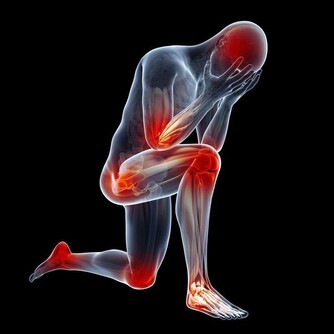

徵兆三:右臂疼痛

前臂和肩膀疼痛。儘管左臂和左肩受到影響最為常見,但嚴重時也會放射到右臂,

當然僅右臂一側出現疼痛者是極為少見的。這個一定要和頸椎病相鑑別。